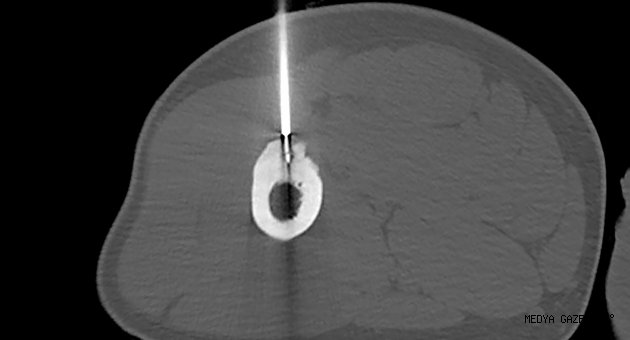

Yaklaşık bir yıldır bacağındaki kemik tümörü nedeniyle yürümekte ve ayağını kullanmakta zorlanan 26 yaşındaki askeri personel A.A.,, tedavi için bugüne kadar hastane hastane dolaştı. Vücudundaki tümör nedeniyle birçok hastaneye giden ve gittiği hastanelerde bir türlü sonuca ulaşamayan A.A, Kahramanmaraş Sütçü İmam Üniversitesi Sağlık Uygulama ve Araştırma Hastanesine (Tıp Fakültesi Hastanesi) başvurdu. Geçirdiği başarılı operasyonla sağlığına kavuşan A.A, işlemin ertesi günü taburcu oldu.“KEMİK TÜMÖRÜNÜ YÜKSEK ISIYLA YAKTIK”Operasyonla ilgili konuşan KSÜ Tıp Fakültesi Radyoloji Ana Bilim Dalı Öğretim Üyesi Doç. Dr. Nursel Yurttutan, şunları söyledi: “Hastamız aktif askerlik mesleğini yapan genç yaşlarda bir erkek. Uzun süredir var olan bacak ağrısı şikâyetiyle tetkik edilirken, uzuv kemiklerinden bir tanesinde küçük boyutta bir lezyon tespit edildi. Bu lezyon ‘osteoid osteoma’ adı ile bilinen iyi huylu bir kemik tümörü türü. Hastanın hayatını tehdit edici bir unsur değil ancak özellikle geceleri artan ağrı semptomu hastaların hayat kalitesini ciddi manada düşürmekte ve uzun süreli ağrı kesici kullanma ihtiyacı hastaları kronik dönemde ağrı kesici bağımlılığına sürüklemektedir. Bunun gibi bir takım kemik tümörlerinde cerrahi tedaviye alternatif olarak özellikle son yıllardaki tıp alanında hızlı gelişmeler sayesinde çeşitli uygulamalar yapılıyor. Biz hastamızda ‘radyofrekans ablasyon’ işlemini uyguladık. Bilgisayarlı tomografi eşliğinde milimetrik boyutta bir kesi alanından kılavuz iğnelerle girip milimetrik boyuttaki lezyon alanına komşu dokulara zarar vermeden ulaştık ve kemik tümörünü ‘radyofrekans ablasyon iğnesi’ ile yüksek ısıyla yaktık. KSÜ Tıp Fakültesi Ortopedi ve Anestezi Bölümlerinin desteği ile gerçekleştirdiğimiz işlemde genel anestezi ile uyutulmadan hastamızın sadece alt ekstremitelerine geçici olarak bölgesel anestezi ve analjezi uygulandı. Bir günlük takip sonrasında da hastamızı taburcu ettik. Literatürde bu işlemin teknik başarı oranının yüzde 95 ila 100 arasında olduğu bildirilmektedir. Üniversitemiz bünyesinde iyi huylu kemik tümörü tedavisi yanında uygun hasta gruplarında cerrahiye uygun olmayan ya da cerrahiye alternatif olabilecek çeşitli tümör tiplerinde radyofrekans ya da mikrodalga ile ablasyon işlemleri minimal invazif olarak, girişimsel radyoloji bölümü öğretim üyelerimiz tarafından gerçekleştirilmektedir.”“GEZMEDİĞİM DOKTOR KALMADI”Bir günde sağlığına kavuşan hasta A.A ise, “Hap kullanmadığım zaman ayağımı taşıyamıyordum. 1 yıldan beri bu hastalık için uğraşıyorum. Gezmediğim doktor kalmadı diyebilirim. Son çareyi burada buldum. Doktorlarımız sağ olsunlar bize çok yardımcı oldular. Operasyon kolay geçti. Ağrılarım dindi. Şimdi rahat yürüyebiliyorum” ifadelerini kullandı.